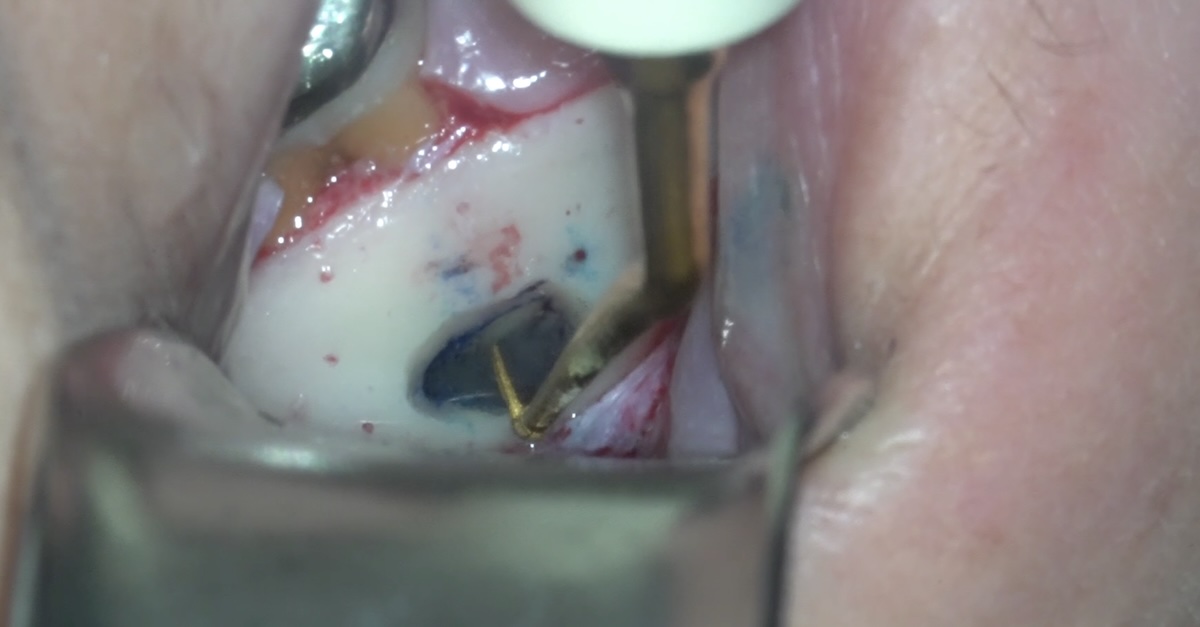

逆根管充填

治療後